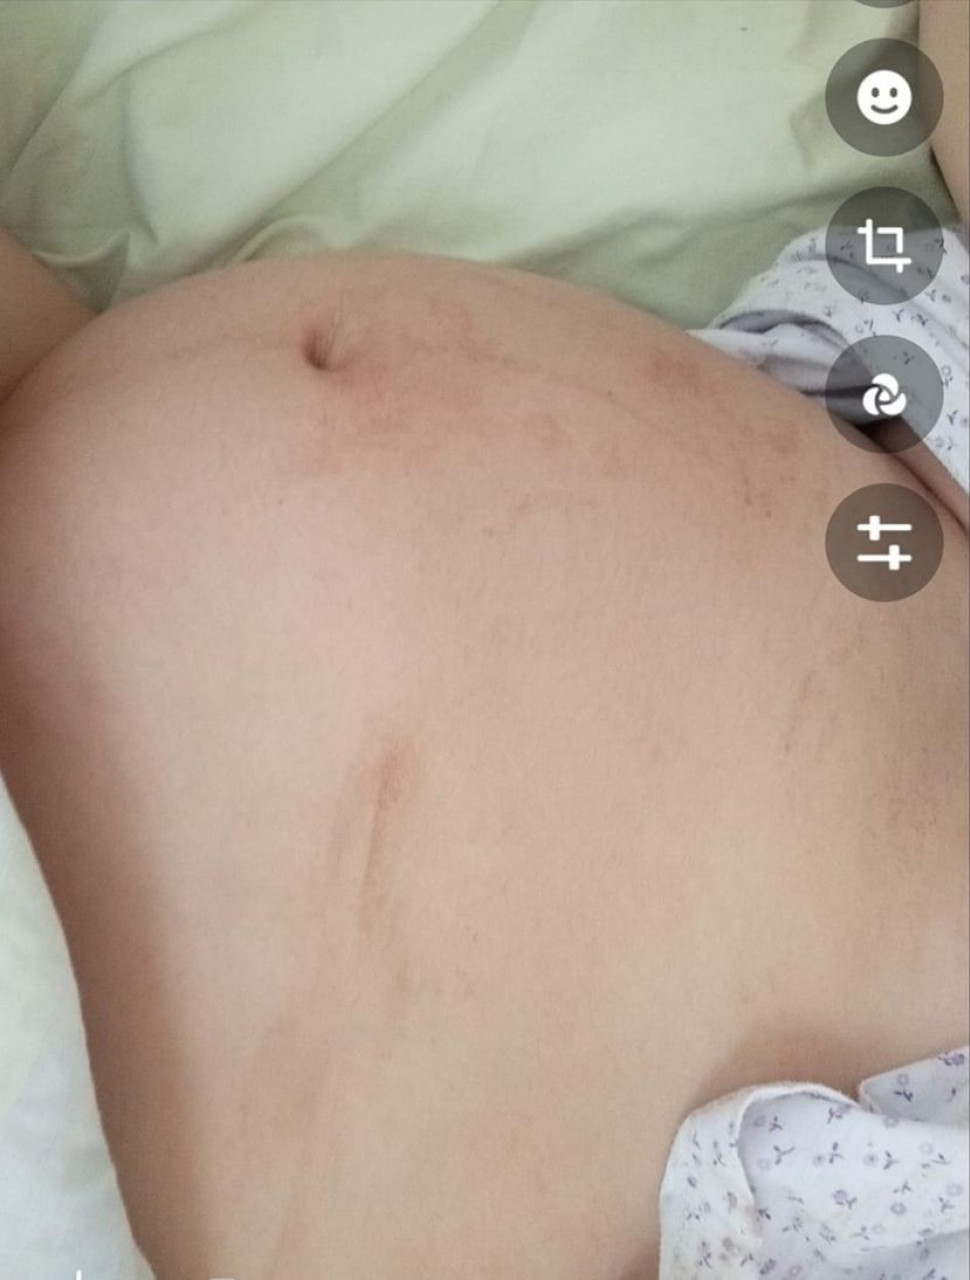

HronikaBeba Marice Mihajlović je preminula prilikom porođaja, zbog loše odluke doktora

Ministarstvo zdravlja uputilo je inspekciju u Opštu bolnicu Sremska Mitrovica, u čijem porodilištu se porodila Marica Mihajlović, čija je beba nakon toga preminula. Pokrenut je unutrašnji nadzor, a inspekcija je upućena juče, odmah po saznanju o slučaju.

Maricu Mihajlović nekoliko dana delilo je od najsrećnijeg trenutka u životu, a onda je, kako je ispričala za Telegraf.rs, doživela horor. Udarci, pretnje i vređanje nije ono što je očekivala da će je dočekati na porođajnom stolu, a ni da će njena beba preminuti.

Jedanestog januara primljena je u Opštu bolnicu u Sremskoj Mitrovici, tada je već prošlo nedelju dana od njenog termina, a nije bilo ni nagoveštaja da bi se mogola poroditi.

Foto: Facebook printscreen/Marica Mihajlović

Dvanaestog ujutru odlazi na pregled, kažu joj da je plodova voda zamućena i počinju sa indukcijom. Ipak, kako se nije dovoljno otvorila za porođaj, oko 17 časova doktor joj saopštava da mora na carski rez i od tada kreću najgori sati života za ovu mladu ženu.

- Vreme prolazi doktora nema, u 18 i 20 dolazi i odlučuje da me ipak porodi prirodnim putem, babice mu govore da ništa ne menja i da moram na carski. On se ipak držao svoje odluke jer je uradio pregled i video da se ništa ne menja i da je beba, još uvek, jako visoko i da ne može da se spusti u karlicu - tvrdi Marica.

Izmučenoj i bez snage daju joj i kiseonik, ali beba i dalje ne mrda od mesta gde je bila, Marica kreće da preklinje doktora da je porodi na carski rez i spase dete, a onda je, kako tvrdi, počinje i stravično maltretiranje.

- Ja ga i pored toga molim samo da mi spasi dete - kroz suze ističe Marica.

SrbijaKada je porođaj napokon krenuo, kako Marica kaže, doktor je video da beba ne može nikako da se rodi, daje joj anesteziju i pokušava da je porodi nasilno.

- Pošto je video da beba ne može da se pusti počeo je da mi skače po stomaku i da me stiska, lomi mi rebro i ja gubim vazduh, a na kraju i svest. Tada se beba zaglavila u karlici i od velikog pritiska se uneredila - objašnjava porodilja koja dodaje da je beba sve to sa plodovom vodom progutala.

Nažalost, iako je dete moglo da uzima kiseonik, nije moglo da izdiše i dolazi do stvaranja mehurića na plućima, a onda i do prestanka rada srca. Doktori je reanimiraju, uključuju na aparate i odmah transportuju za Novi Sad.

- Beba je samo par sati bila živa, mene su sutradan oko 13 časova pozvali i rekli da je preminula. Oštetio joj se i mozak, da je preživela imala bi posledice - priča utučena Marica.

Foto: Facebook printscreen/Marica Mihajlović

Nakon stravičnog iskustva koje je doživela sa doktorm M.M. rešila je da svoju tragediju podeli sa drugim sugrađankama kako bi ih upozorila, međutim, njoj se javio veliki broj žena koje su doživele, nažalost, vrlo slično iskustvo.

- Meni se javila žena, 2022. godine je doživela maltene isto, beba joj je umrla posle 3 meseca - tvrdi Marica.

Ona i njen suprug Danijel apelovali su na sve institucije da se ovaj slučaj istraži, a da doktor M.M. dobije otkaz.

- Jedina mi je želja da se ovome stane na put, nisam prva kojoj se ovako nešto desilo. Babice mi govore da imam svu njihovu podršku i šta god bude trebalo da će svedočiti. Pazite se ovog čoveka, ovo je akušersko nasilje, moje dete je uzeo, mog malog anđela koje sada leži u grobu - navela je neutešna majka.

Foto: Facebook printscreen/Marica Mihajlović

Opšta bolnica u Sremskoj Mitrovici povodom ovog događaja otkrila je za Telegraf da je unutrašnji nadzor već pokrenut.

- Obaveštena je zdravstvena inspekcija, i po obavljenim postupcima, a vezanim za navedeni događaj, bićete obavešteni - rekli su.